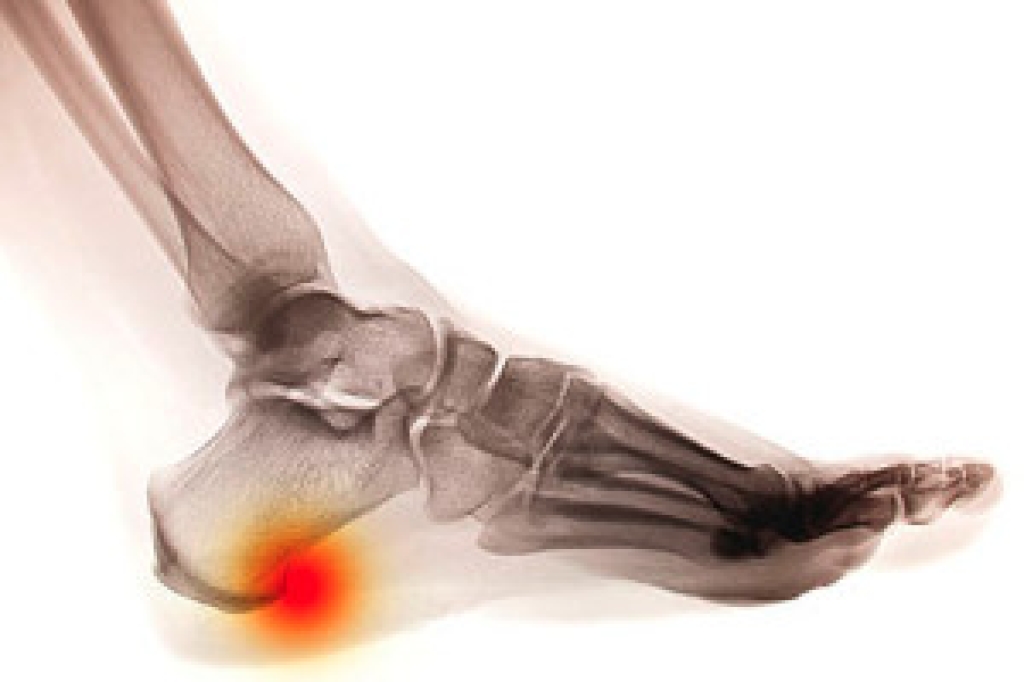

When there is excessive stress in the heel, new bone is formed to protect the heel against fractures. This is known as a heel spur and often feels like a bump in the heel. It typically begins as cartilage and then progresses into solid bone. They’re present in about half the population, although not everyone has pain. The most common cause of heel spurs is plantar fasciitis. If pain is experienced, it’s usually in the morning or after resting. Typically, after the first few steps, the pain will improve as the foot gets used to the movements. Certain exercises may also help relieve the pain. Placing the affected foot on a tennis ball while rolling it around may be beneficial in relaxing the muscles. Additionally, bending the knees while moving up and down may provide additional relief.

Heel spurs are formed by calcium deposits on the back of the foot where the heel is. This can also be caused by small fragments of bone breaking off one section of the foot, attaching onto the back of the foot. Heel spurs can also be bone growth on the back of the foot and may grow in the direction of the arch of the foot.